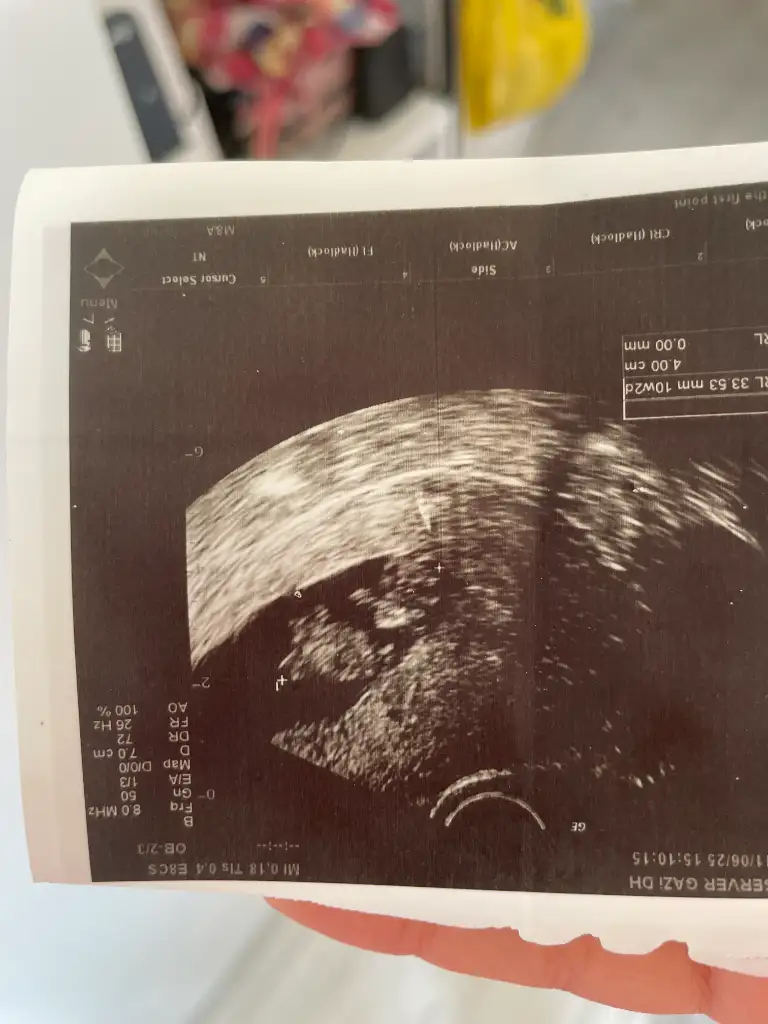

İlk resimde erkeğe benziyor ama kalça kemiği de olabilir dedi, 13 haftalık tam, bacağını kapatıyor, arkadan da boş görünüyor, pipi olsa arkadan görünür müNub şekline göre yorum yaptım öğrenebildiniz mi

Kız sanırım bacak arası boş görünüyor ben size benim resmi ekleyeyim videodan çektim 14 haftalıktı öğrendiğim deİlk resimde erkeğe benziyor ama kalça kemiği de olabilir dedi, 13 haftalık tam, bacağını kapatıyor, arkadan da boş görünüyor, pipi olsa arkadan görünür mü

Sizinki kız miKız sanırım bacak arası boş görünüyor ben size benim resmi ekleyeyim videodan çektim 14 haftalıktı öğrendiğim de

ErkekSizinki kız mi